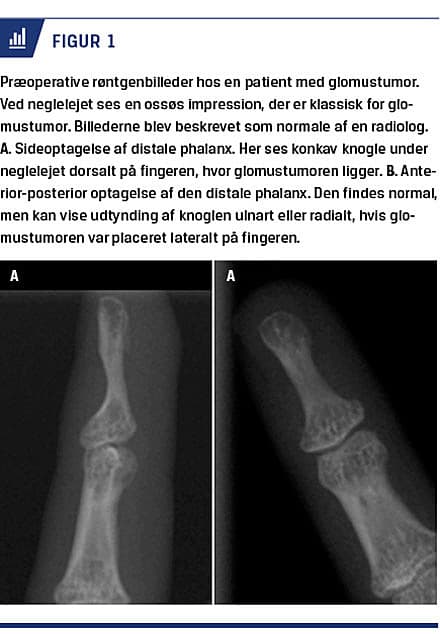

tumorerne ofte er 0-5 mm i diameter [8] og dermed svære at identificere ved almindelige billedsnit [15, 18]. Ved UL-skanning kan man ofte undervurdere størrelsen af en tumor, men skanningen kan bidrage til at fastslå den anatomiske lokalisation i fingeren [17, 20]. Doppler-UL-skanning kan være effektiv, når man skal bekræfte tilstedeværelsen af en vaskulariseret tumor [21]. I 36% af tilfældene kan et almindeligt røntgenbillede af fingeren vise en ossøs defekt [19, 24]. Figur 1 viser røntgenbilleder af en distal phalanx med ossøs impression i neglelejet hos en patient med en 5 × 5 mm stor glomustumor. Hvis en patient har den klassiske kliniske triade af symptomer, er der konsensus om, at det er indikation for eksplorativ kirurgi trods negativt resultat af billeddiagnostik [4, 15, 17, 18].